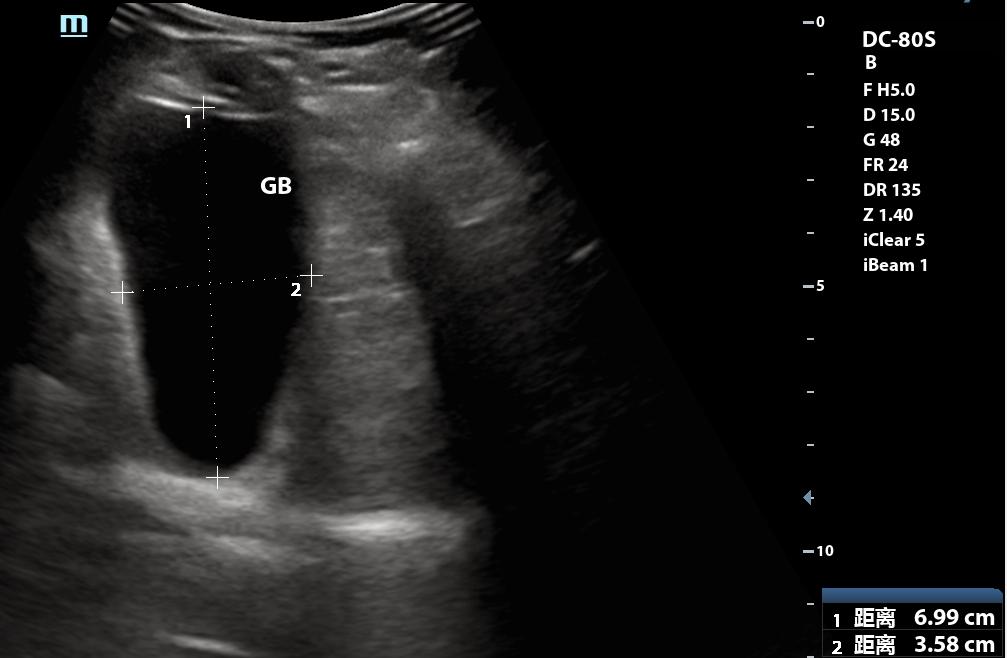

终于滚出来了

此时我明确地告诉李四“你确实有结石”,李四也回应了“哦”,估计心想“我早就知道了”

后来李四走后,我查了查病史,原来两年前做了彩超后,又做了CT,CT提示有胆囊结石,这次先做了CT,再做的彩超,上次超声没报结石,而CT报了,这次CT也报了,所以李四很蒙圈,到底有没有结石。而我也差点没发现。